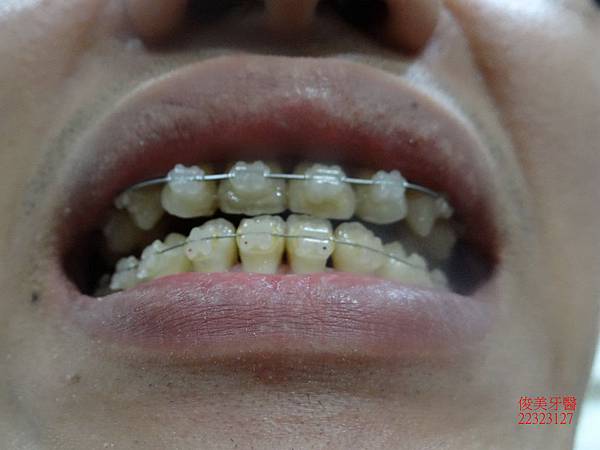

治療中~~~~

患者覺得非常開心,因為朋友在其他診所治療,都不敢相信他的療程進展如此神速~~~~~

上排牙齒已經恢復到正常咬合的位置點囉!!

患者將以前做的假牙更換為全瓷牙冠,改善美觀問題。